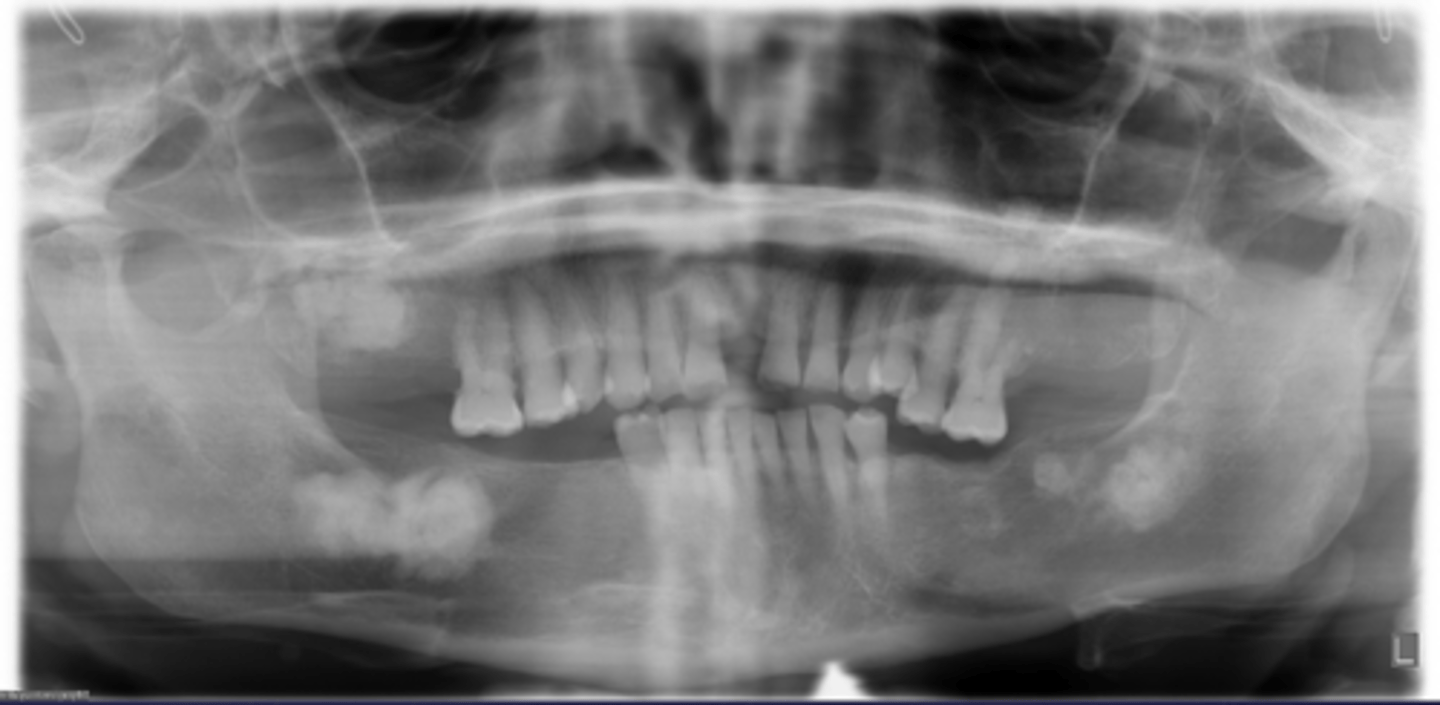

how would you describe this lesion?

A. well-defined, periapical radiolucent lesion associated with #24 and 25

B. ill-defined, periapical radiolucent lesion associated with #24 and 25

C. well- defined, multilocular periapical lesion associated with tooth number 24 and 25

D. mixed density, periapical lesion associated with teeth number 24 and 25

- Also note loss of apical lamina dura of 24, 25

What category would this lesion be part of?

Dysplasia

What would be a differential diagnosis for this lesion?

PCOD (stage 1)